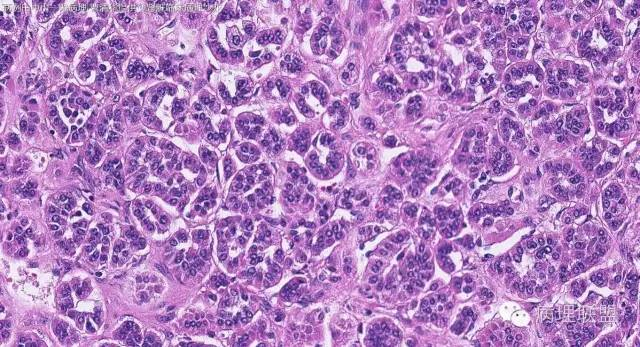

女性,50岁,肾上腺肿物(影像及手术均确认肿物位于肾上腺,界限清楚)。血压升高。(病例由 中山一院病理 曹清华提供,致谢!)

CK,Vimentin,CD56 阳性

inhibina, melana, syn, cga, wt-1, cd57均阴性

从肿瘤的位置及镜下与肾上腺皮质的关系看,应该像是皮质来源肿瘤。假腺样结构的皮质腺瘤没有见过,似乎文献也还没查到。另外inhibina, melanA, syn均阴性(肿瘤旁正常皮质阳)感觉有点迷惑。。。请老师指教,有相关文献么?@武警嘉兴医院 周泉

这个我再仔细看下。但,我们这例腺管结构不像是粘附差所致,是真的腺管;间质目前还没有看到有间质粘液变性区域;inhibina, syn, menlana是真的不阳,灶性都没有...